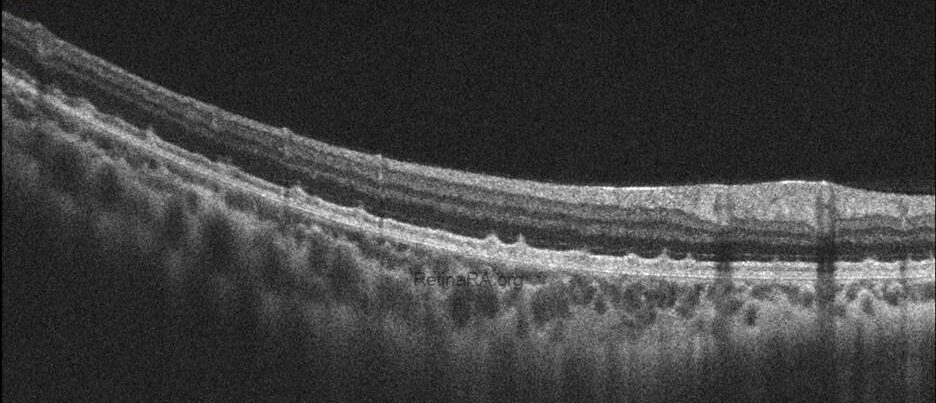

Optical coherence tomography (OCT) provides valuable structural information in fundus albipunctatus. OCT imaging typically demonstrates focal hyperreflective material originating from the RPE and projecting into the outer retinal layers, correlating with the punctate lesions seen on fundus examination. On fundus autofluorescence imaging, a diffusely reduced background autofluorescence is commonly observed, reflecting impaired retinoid metabolism and RPE dysfunction related to disruption of the visual cycle.